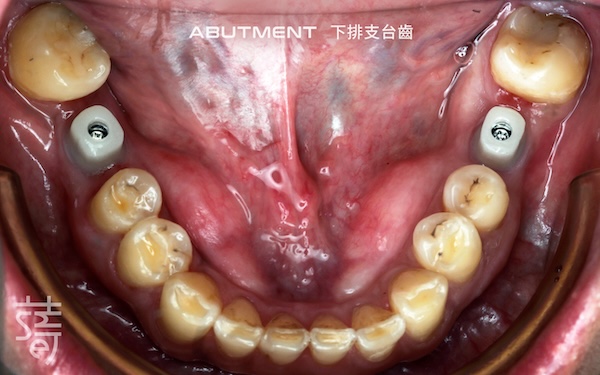

第二階段:植牙重建缺牙區 Stage Two: Implants for Missing Molars

針對缺牙已久的後牙區進行植牙,恢復後牙支撐,避免整體咬合繼續崩塌,讓口腔受力更均衡。

Implants were placed in the long-missing molar areas to restore support, prevent further bite collapse, and balance oral forces.